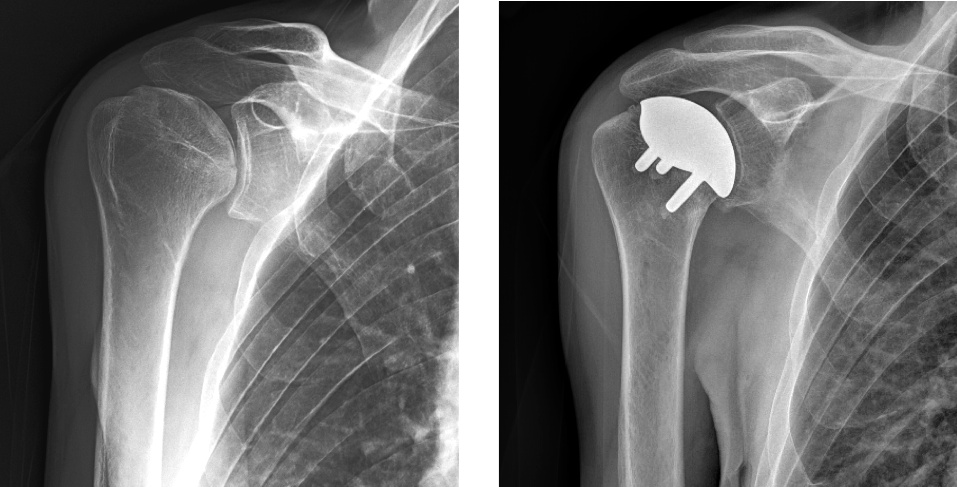

Pre-operative and post-operative x-rays of a patient with glenohumeral arthritis, treated with anatomic total shoulder replacement.

An anatomic total shoulder replacement involves resurfacing of the glenoid or "socket" with a plastic liner (high molecular weight polyethylene) and replacing the ball at the top of the arm (humeral head) with a metallic ball (usually cobalt chrome). Recovery is delayed after this procedure because the front rotator cuff tendon (subscapularis tendon) has to be cut to perform the procedure and then repaired once the implants are in place. This surgery is very successful at reducing pain and improving overall function. To be a candidate for an anatomic total shoulder replacement, you must have an intact rotator cuff, adequate glenoid bone stock to receive the plastic socket implant, and have significant pain refractory to non-operative treatments.